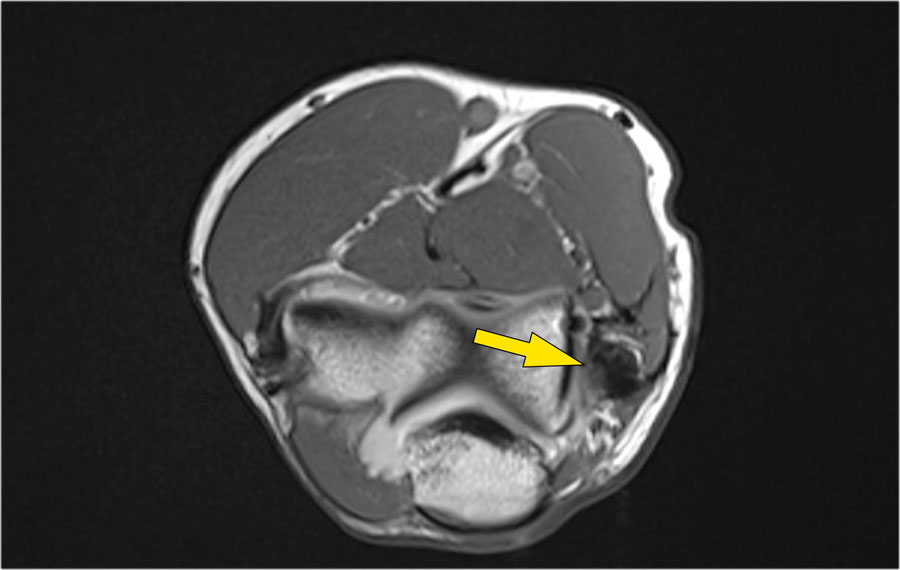

Khi quan sát trên lát cắt ngang (axial), chúng ta có thể nhận thấy sự hình thành gai xương khổng lồ.

Lưu ý rằng dây thần kinh trụ (mũi tên màu xanh) nằm cạnh các gai xương này và những bệnh nhân này có thể biểu hiện bệnh lý thần kinh trụ.